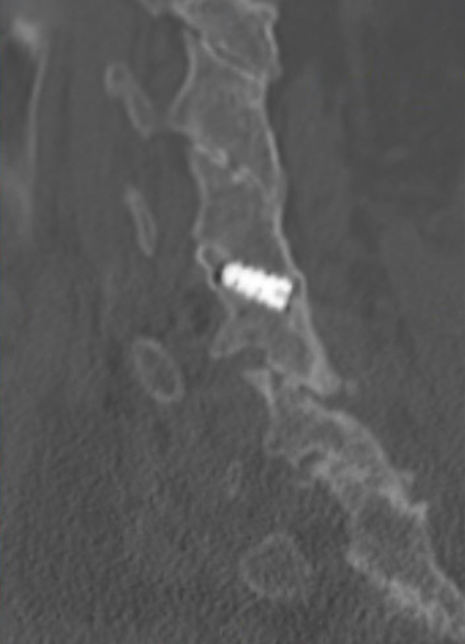

Sagittal CT image showing left anterior/posterior bone bridging.